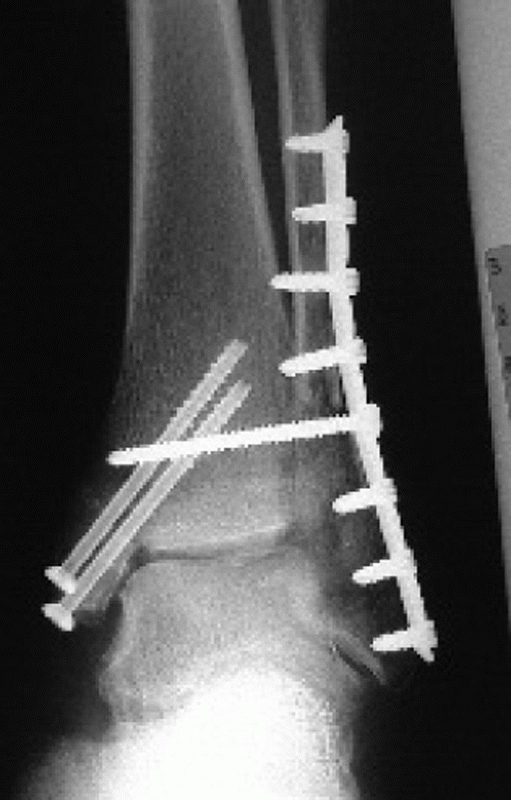

adequate reduction with the foot in neutral have been established and

validated.95,177

Parameters that suggest unstable fracture patterns include lateral

malleolar displacement greater than 2 mm with resultant talar shift on

the AP or lateral, significant medial malleolar displacement, deltoid

ligament disruption defined by greater than 5 mm medial clear space,

syndesmosis injury identified by tibial-fibular clear space greater

than 5 mm or tibial-fibular overlap of less than 10 mm (both on the

AP), or a tibial-fibular overlap of less than 1 mm on the mortise view (Fig. 57-3).